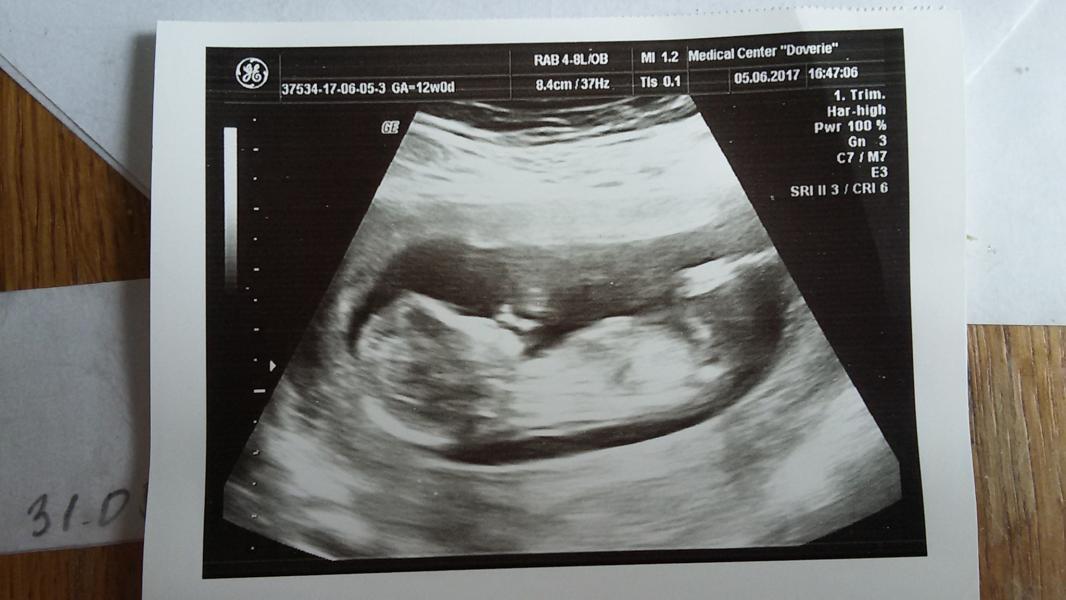

Ну вот и сделали первый скрининг ровно в 12 недель. Очень переживала))) Всё в норме малыш очень подвижный, дали первый снимок. Нетерпится узнать пол, но врач сказала что на этом сроке ещё не видно кто, что смотрят начиная с 16 недели...)))